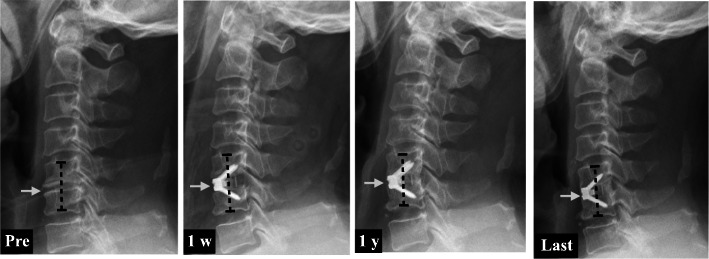

Fig. 3.

Case report: A middle-aged patient who had undergone C5/6 ACDF using the Zero-P device. The mean IH was increased significantly from 6.52 mm preoperatively to 10.37 mm at 1 week, and then it decreased to 7.84 mm at 1 year and 7.39 mm at the last follow-up (white arrows)

The intervertebral height (IH) was effectively improved in all patients. The average IH rose significantly from 6.72 mm preoperatively to 10.46 mm 1 week before being progressively reduced to 9.58 mm at 3 months, 8.73 mm at 6 months, 7.58 mm at 1 year, and 7.50 mm at the last follow-up. Thus, the IH changed subtly 1 year after ACDF (Fig. 2). Our data revealed no clear association between the postoperative disc height change and any clinical outcomes in the 1st year after ACDF surgery.